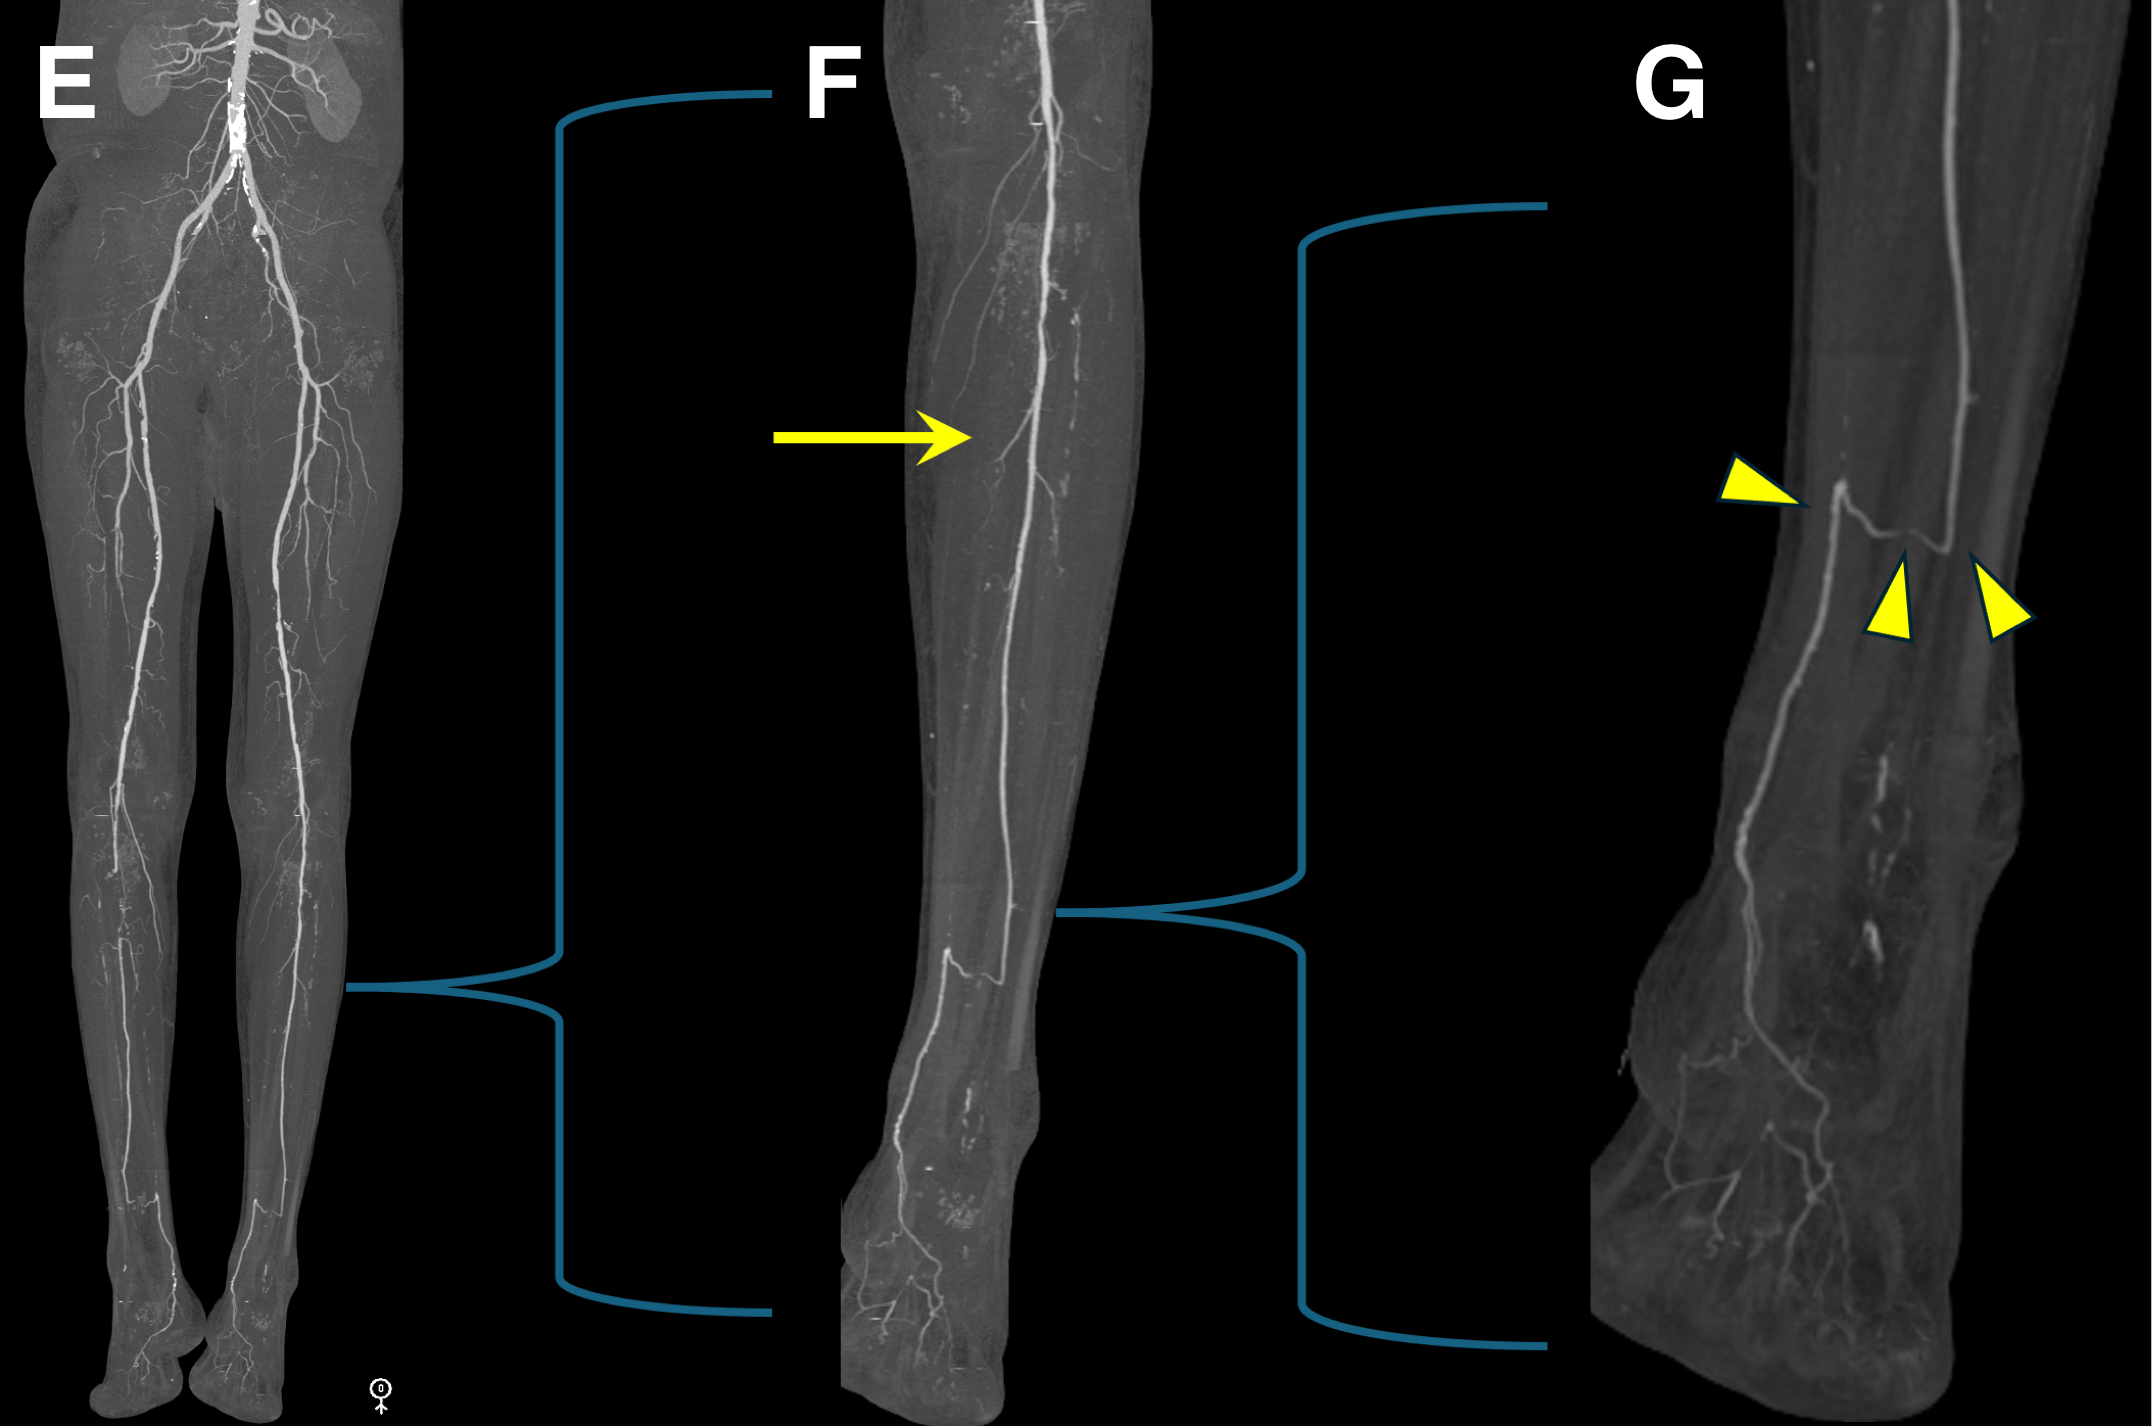

Figure E-G: Left leg.

Figure E. Overview bone-segmented maximum intensity projection (MIP) image shows no significant inflow or femoropopliteal steno-occlusive disease.

Figure F. MIP image of left calf shows occlusion of the posterior and anterior tibial arteries with patent peroneal artery to the distal calf (arrow).

Figure G. Small field of view MIP image shows peroneal reconstitution of the posterior tibial artery, which continues patent across the ankle into the foot. This anatomy is similar to the right side. The reason the patient was more symptomatic on the right is likely related to the absence of the proximal peroneal occlusion on the left side.